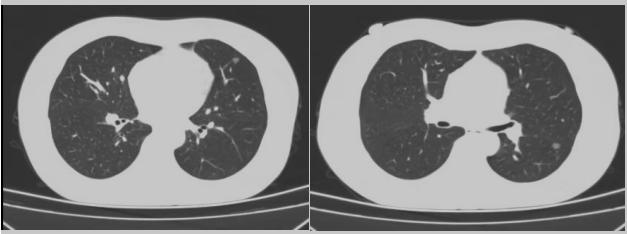

在醫(yī)學(xué)上的定義,肺結(jié)節(jié)就是在肺葉內(nèi)小于等于3公分的結(jié)節(jié)影,密度比正常肺葉要高,周圍有肺葉包裹的,臨床缺乏特異性癥狀和體征,大多數(shù)通過體檢、特殊人群篩查或者診療過程常規(guī)檢查及隨診發(fā)現(xiàn)。多發(fā)肺結(jié)節(jié)是指肺內(nèi)存在兩個(gè)或以上直徑均小于等于3cm的病灶,影像學(xué)上常表現(xiàn)為若干個(gè)含磨玻璃影的結(jié)節(jié),近年來肺部多發(fā)肺結(jié)節(jié)的患者越來越多,最新統(tǒng)計(jì)數(shù)據(jù)顯示,雙肺多發(fā)結(jié)節(jié)患者占所有肺結(jié)節(jié)患者總數(shù)的18%。

病例二:42歲的范女士,半年前體檢時(shí)發(fā)現(xiàn)雙側(cè)多發(fā)肺結(jié)節(jié),平時(shí)沒有什么不適。四個(gè)月后再次復(fù)查胸部CT,左上肺及下肺多發(fā)的磨玻璃結(jié)節(jié),其中下葉9mm的結(jié)節(jié)定為高危病灶。看到結(jié)果范女士坐不住了,多方打聽慕名找到了市二院院長王瑾,經(jīng)“肺結(jié)節(jié)MDT”團(tuán)隊(duì)會(huì)診后,決定手術(shù)治療。入院后,胸外科副主任醫(yī)師薛飛詳細(xì)與范女士溝通,并利用Mimics做好了術(shù)前肺部三維重建手術(shù)規(guī)劃,打消了范女士心中的顧慮。經(jīng)過前期充分準(zhǔn)備后,歷經(jīng)1小時(shí)30分,完成“胸腔鏡下左肺上葉舌段楔切及左肺下葉背段切除術(shù)”,術(shù)后病理檢查結(jié)果確診為左肺微浸潤性腺癌。在胸外科團(tuán)隊(duì)的悉心照顧下,患者術(shù)后恢復(fù)良好,一周后順利出院。